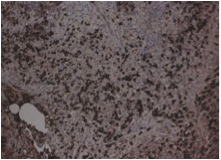

Excisional biopsy of submandibular gland with a diagnostic testing was performed. It showed lymphoid infiltrate with marked atrophy and perilobular and septal sclerotic fibrosis. The lymphoid infiltrate mainly consisted of small lymphocytes and large number of plasma cells. Immunohistochemical studies found most of the plasma cells positive for IgG and IgG4. So, the pathology suggested chronic sclerosing sialadenitis, consistent with IgG4-related disease. The ampulla specimen obtained in previous ERCP was also positive in IgG4 staining. The serum IgG4 level was checked and elevated to 102.9 g/L (normal range <2).

We reviewed the case and requested IgG4 staining for the transbronchial biopsy that obtained 3 months ago. The resulted showed many of the plasma cells positive cytoplasmic staining for both IgG and IgG4 (Fig 4A, 4B, 4C, 4D). It confirmed the pulmonary involvement of IgG4-related disease.